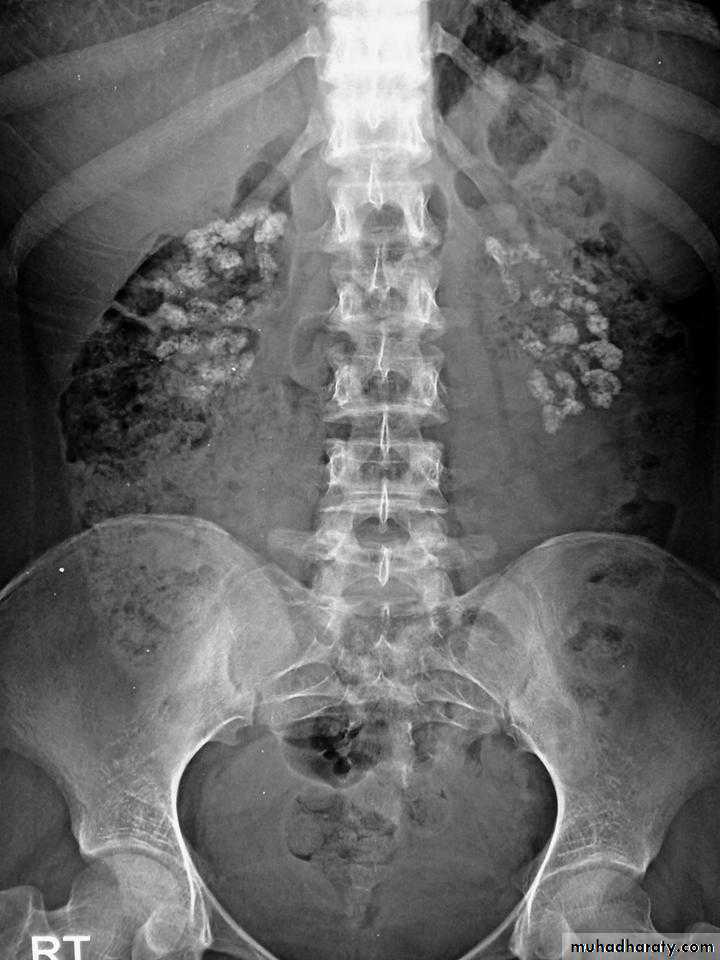

Primary hyperparathyroidism(Radiological features)

Characteristic changes on plane X ray are:

Scattered opacities within the renal outline (nephrocalcinosis)

renal stones

Soft tissue calcification affecting arterial walls, hands or cornea